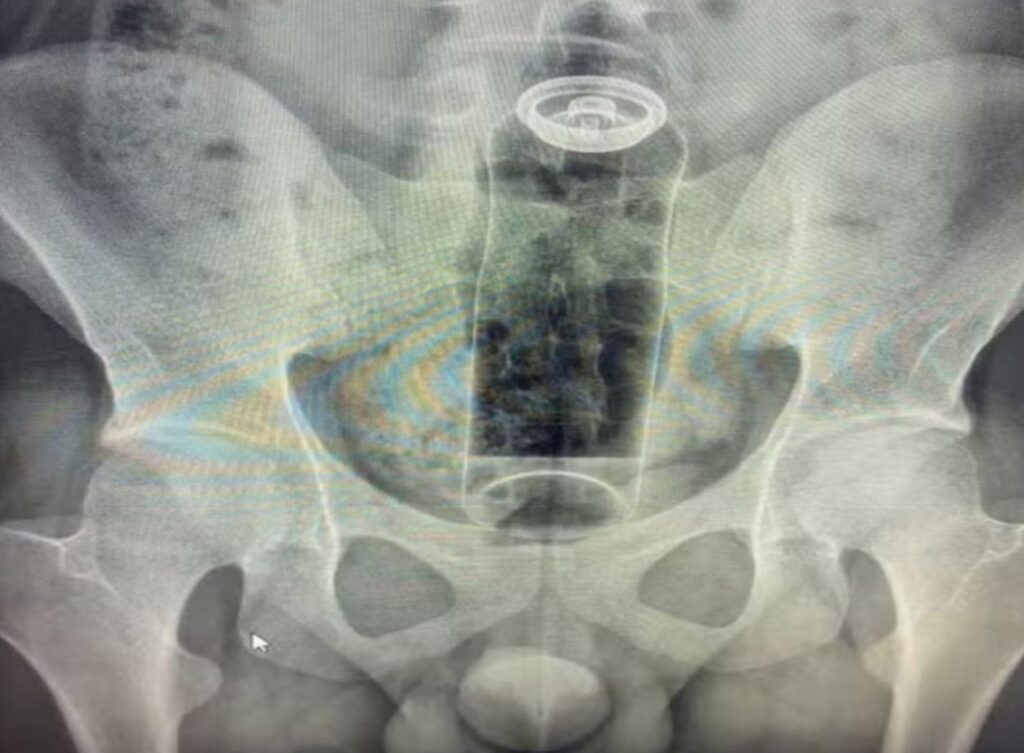

Um jovem de 19 anos precisou de atendimento hospitalar após uma situação inusitada durante uma brincadeira íntima terminar em emergência médica. Durante o ato, um frasco de desodorante acabou sendo introduzido pelo reto e, devido aos movimentos naturais do organismo, avançou para uma região mais profunda do intestino.

Ao perceber que não conseguiria remover o objeto por conta própria e sentir desconforto crescente, o rapaz buscou ajuda médica. Exames realizados no hospital confirmaram a presença do corpo estranho em uma área que impossibilitava a retirada manual, tornando necessária a intervenção de uma equipe especializada.